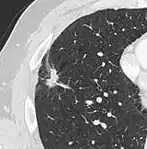

- Pleural retraction is far more common in cancers.[9] It is the pulling of visceral pleura towards the nodule.[9]

Nodule with pleural retraction.[9]

In this case, pleural retraction is seen as a triangular fat component.[9]